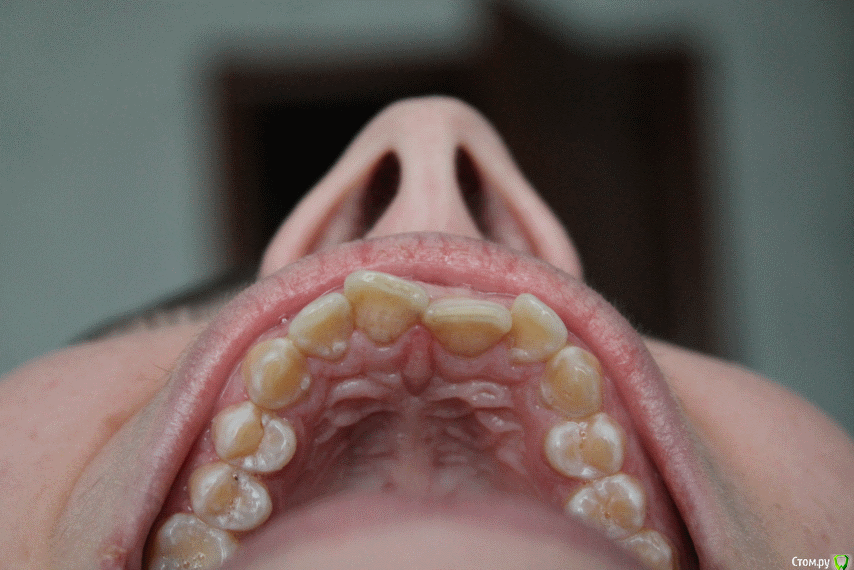

aleksandrovna_o Опубликовано 18 ноября, 2015 Поделиться Опубликовано 18 ноября, 2015 Здравствуйте.Мне 26 лет, дистальный глубокий прикус, на ВЧ скученность зубов. Все зубы свои, удалены 8-е на нижней челюсти.3 ортодонта сказали,что нужно удалять 4-ки, если их не удалить, то увеличится сагиттальная щель, челюсть ещё больше выдвинется вперёд, изменится профиль.4-е зубы не хочу удалять. Возможно ли в моей ситуации удалить 8-е на ВЧ и (или) сделать сепарацию, чтобы освободить место. Мне даже не нужно, чтобы зубы идеально встали в один ряд, просто хоть чуть-чуть исправить?Очень боюсь, что черты лица изменятся (впалые щёки, выраженные скулы). Очень рассчитываю на Ваш ответ. Снимки прилагаю. Ссылка на комментарий